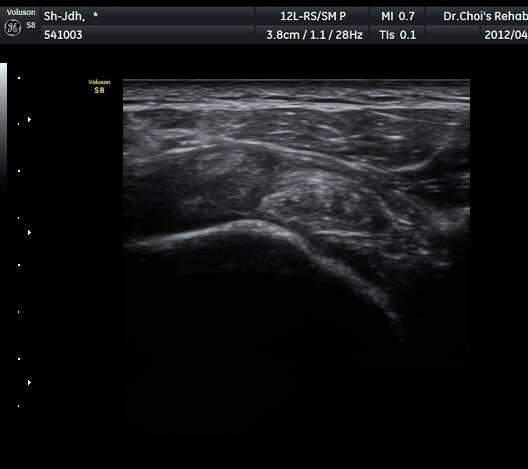

¾î±ú µÚ °üÀý¼ø °Ë»ç¿¡¼­ °üÀý¼ø Ç¥Ãþ¿¡ Àú¿¡ÄÚ ¼ö¾×Àú·ù°¡ °üÂûµÊ(»çÁø 4).

ŽÃËÀÚ¸¦ Á» ´õ µÚ·Î À̵¿ÇÏÀÚ °üÀý¼ø ³»Ãø °¡½Ã°üÀý¿À¸ñÆÐÀÓ(spinoglenoid notch)¿¡

¿øÇü¸ð¾çÀÇ Àú¿¡ÄÚ ³¶Á¾ÀÌ °üÂûµÊ(»çÁø 5, 6).